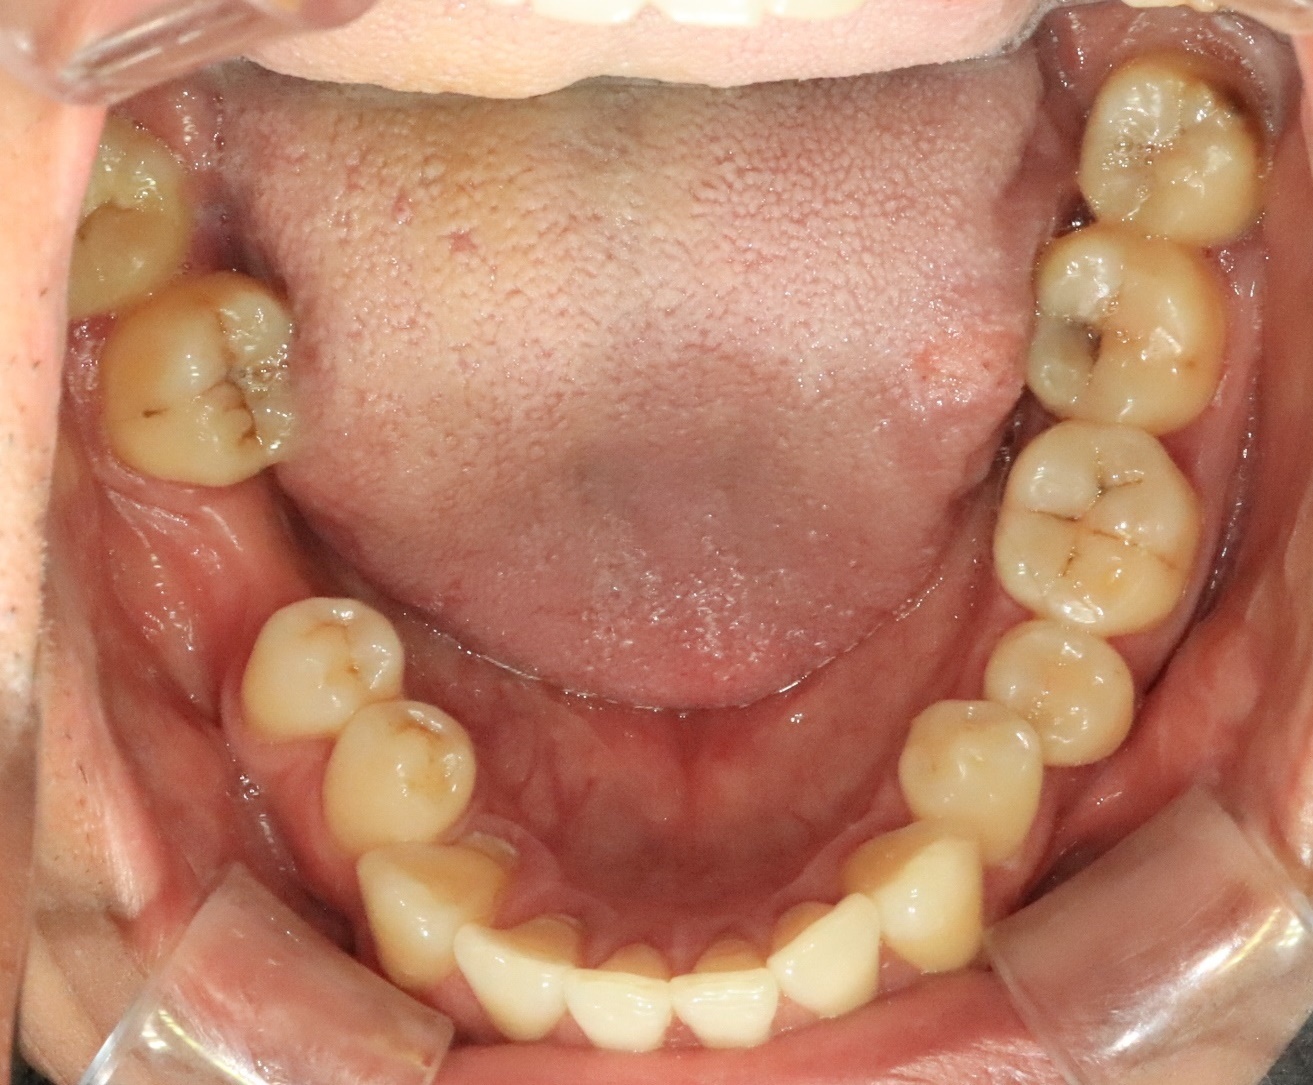

신경치료 후 크라운

Before

After

근관치료 후 치아 보호를 위한 크라운